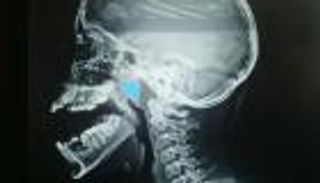

وأوضحت أن "الغشاء المخاطي للأنف يشكل حاجزاً أمام تغلغل مسببات الأمراض المختلفة في الجسم. وعندما تتعطل وظيفة الحاجز، يزداد خطر العدوى. وتحدث مضاعفات قد تؤدي للإصابة ببالتهاب الأنف المزمن والتهاب الجيوب الأنفية والتهاب الأذن الوسطى والتهاب الشعب الهوائية أو الالتهاب الرئوي".